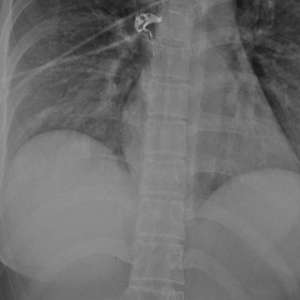

Силиконовый имплант стал настоящим спасителем для девушки, остановив пулю, которая была направлена прямо в её сердце.

Во время обследования врачи обнаружили, что пуля сломала ребро с правой стороны грудной клетки. Удивительно, но она вошла в левую молочную железу и, рикошетом от импланта, попала в правую.